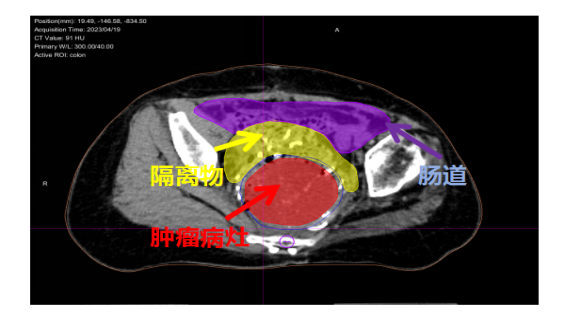

重(碳)离子治疗靶区勾画,瘤体与危及器官间手术置入隔离组织物,为目标肿瘤与周围正常组织提供了足够的距离,从而可以给肿瘤以充足的根治剂量。

靶区勾画:GTV-红色 结肠-紫色 隔离组织物-黄色

治疗前肿瘤8.8×7.1cm,左图为MRI的T1轴位,中图为T2轴位,右图为T1矢状位